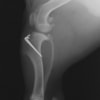

本症例は、走った後に左後肢を挙上していることを主訴に来院されました。触診時に左膝関節のクリック音を聴取、レントゲン検査にて左脛骨の前方変位が認められました。術中に、前十字靱帯の断裂及び内側半月板の損傷、内側の軟部組織の顕著な腫脹を確認。半月板切除、TPLOを実施しました。周囲組織への炎症の波及もあったため回復に時間を要しておりますが、徐々に跛行頻度は減少傾向にあり、現在も経過観察中です。術前に約29°あったTPAは術後に約10°まで矯正されました。

手術前後のTPA(脛骨高平部の角度)を測定しています。

約29°から約10°へ矯正されています。